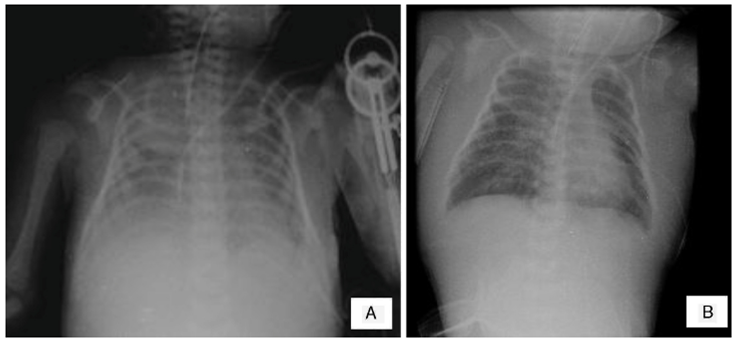

En las últimas radiografías se observó borramiento de los ángulos costodiafragmáticos, opacidad en pulmón izquierdo y engrosamiento de los tejidos blandos (Figura 1A). No se puede descartar zona de consolidación. Se puede observar el edema de tejidos blandos de manera difusa hasta cuello y un infiltrado pulmonar sugerente de edema pulmonar agudo (Figura 1B).

Figura 1 A) Se aprecia engrosamiento de tejidos blandos y borramiento de ángulos costodiafragmáticos. B) Persistencia de edema de tejidos blandos en tórax y cuello y datos de edema pulmonar.